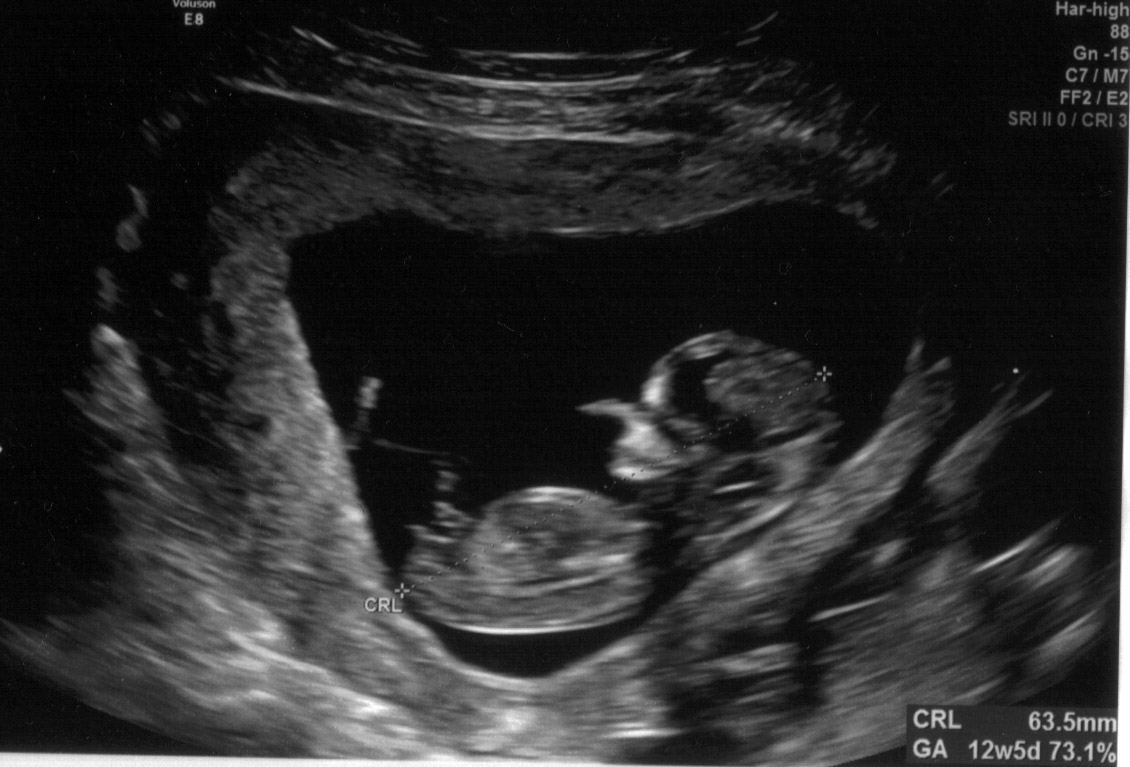

This is my NT scan at 12 weeks. Any guesses on the nub?? Attachment 24079Attachment 24080